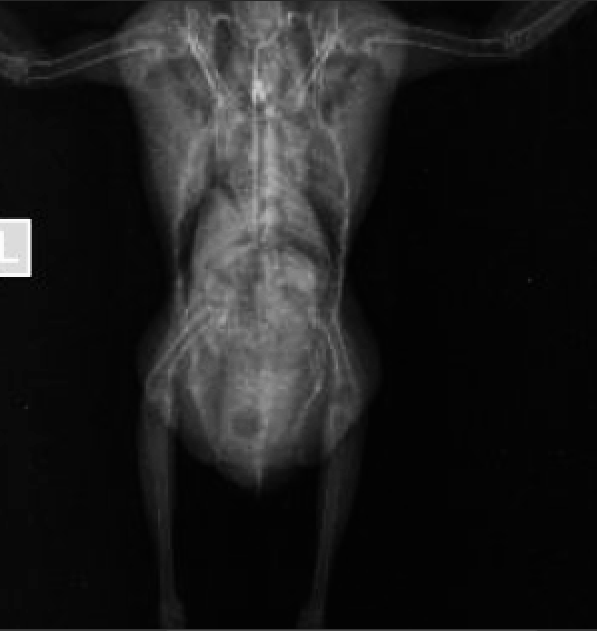

Сделала рентген.

Small Skeletal _ 10 kg-Paw LAT-14.09.2020-17_39_47-114.JPEG

Птица худеет , сама не ест, приходится заставлять, но довольно активная, все время пытается улететь. Какое количество еды ей необходимо? Правой лапой лучше цепляется, чем левой, но на лапы не становится. Когда передвигается по коробке отталкивается лапами и помогает себе крыльями. Какое количество еды ей необходимо? Какое лечение?

По проблеме- это самка.

На ВД проекции в брюшной полости фиксируется округлое образование с капсуле, не являющееся желудком. Оно же видно (туманно) и на латеральной проекции. Так же возможно есть еще пара таких образований в зоне расположения яичника.

Так как сезон размножения давно прошел- можно предположить нечто вроде кистозных образований, которые вероятно пережимают нервы, идущие к нижним конечностям.

И напишите где рентген делали- хорошо разложена птица.